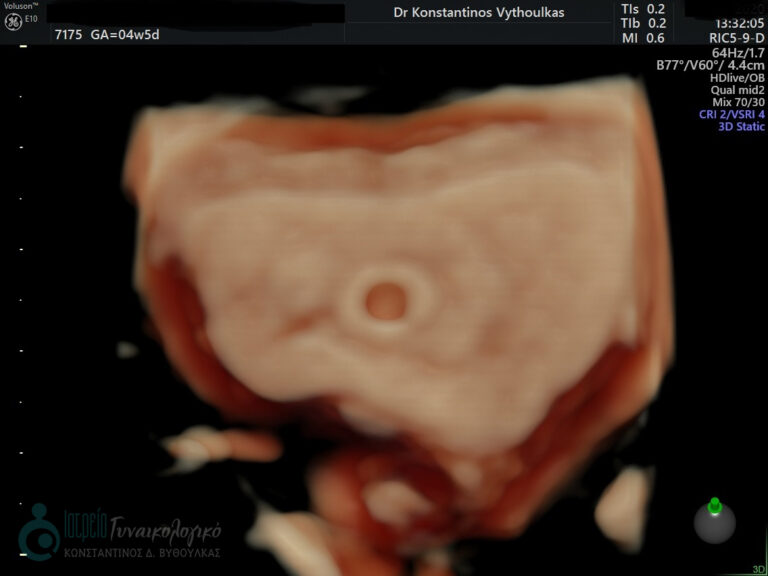

- Υπερηχογραφική εξέταση, η οποία συμβάλλει στη διαπίστωση της ενδομήτριας κύησης και αποκλεισμό της έκτοπης κύησης. Επιπλέον, μπορεί να διαπιστώσει εάν πρόκειται για μονήρη ή πολύδυμη κύηση, να ανιχνεύσει την εμβρυϊκή καρδιακή λειτουργία μετά τις 6 εβδομάδες και να προσδιορίσει υπερηχογραφικά την ηλικία κύησης, με βάση το κεφαλουραίο μήκος του εμβρύου μετά τις 8 εβδομάδες.